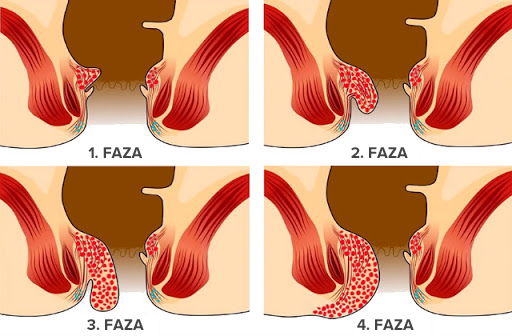

Faze hemoroida

Na internetu sam pronašla sliku sličnu onoj koju sam imala. Na lijevoj strani, treća faza hemoroida (koju sam ja imala).